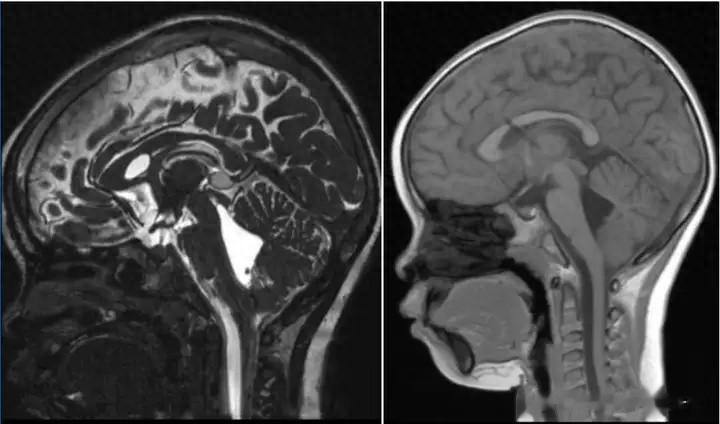

然而,命运似乎并未就此放过她。2024年9月,她再次出现发作性头晕、嗜睡,甚至唤醒困难的症状,这些症状持续了两周,丝毫没有缓解的迹象。9月中旬,头颅影像检查结果如同晴天霹雳:第四脑室扩张、侧脑室呈裂隙状,而分流术后状态的脑室系统似乎也未能发挥应有的作用。尽管医生尝试调整分流管压力,但症状的改善只是昙花一现,随后又继续恶化。近五天来,她反复出现睡眠增多、进食减少的情况,这让她的父母陷入了深深的绝望。

患儿出院前头颅CT检查